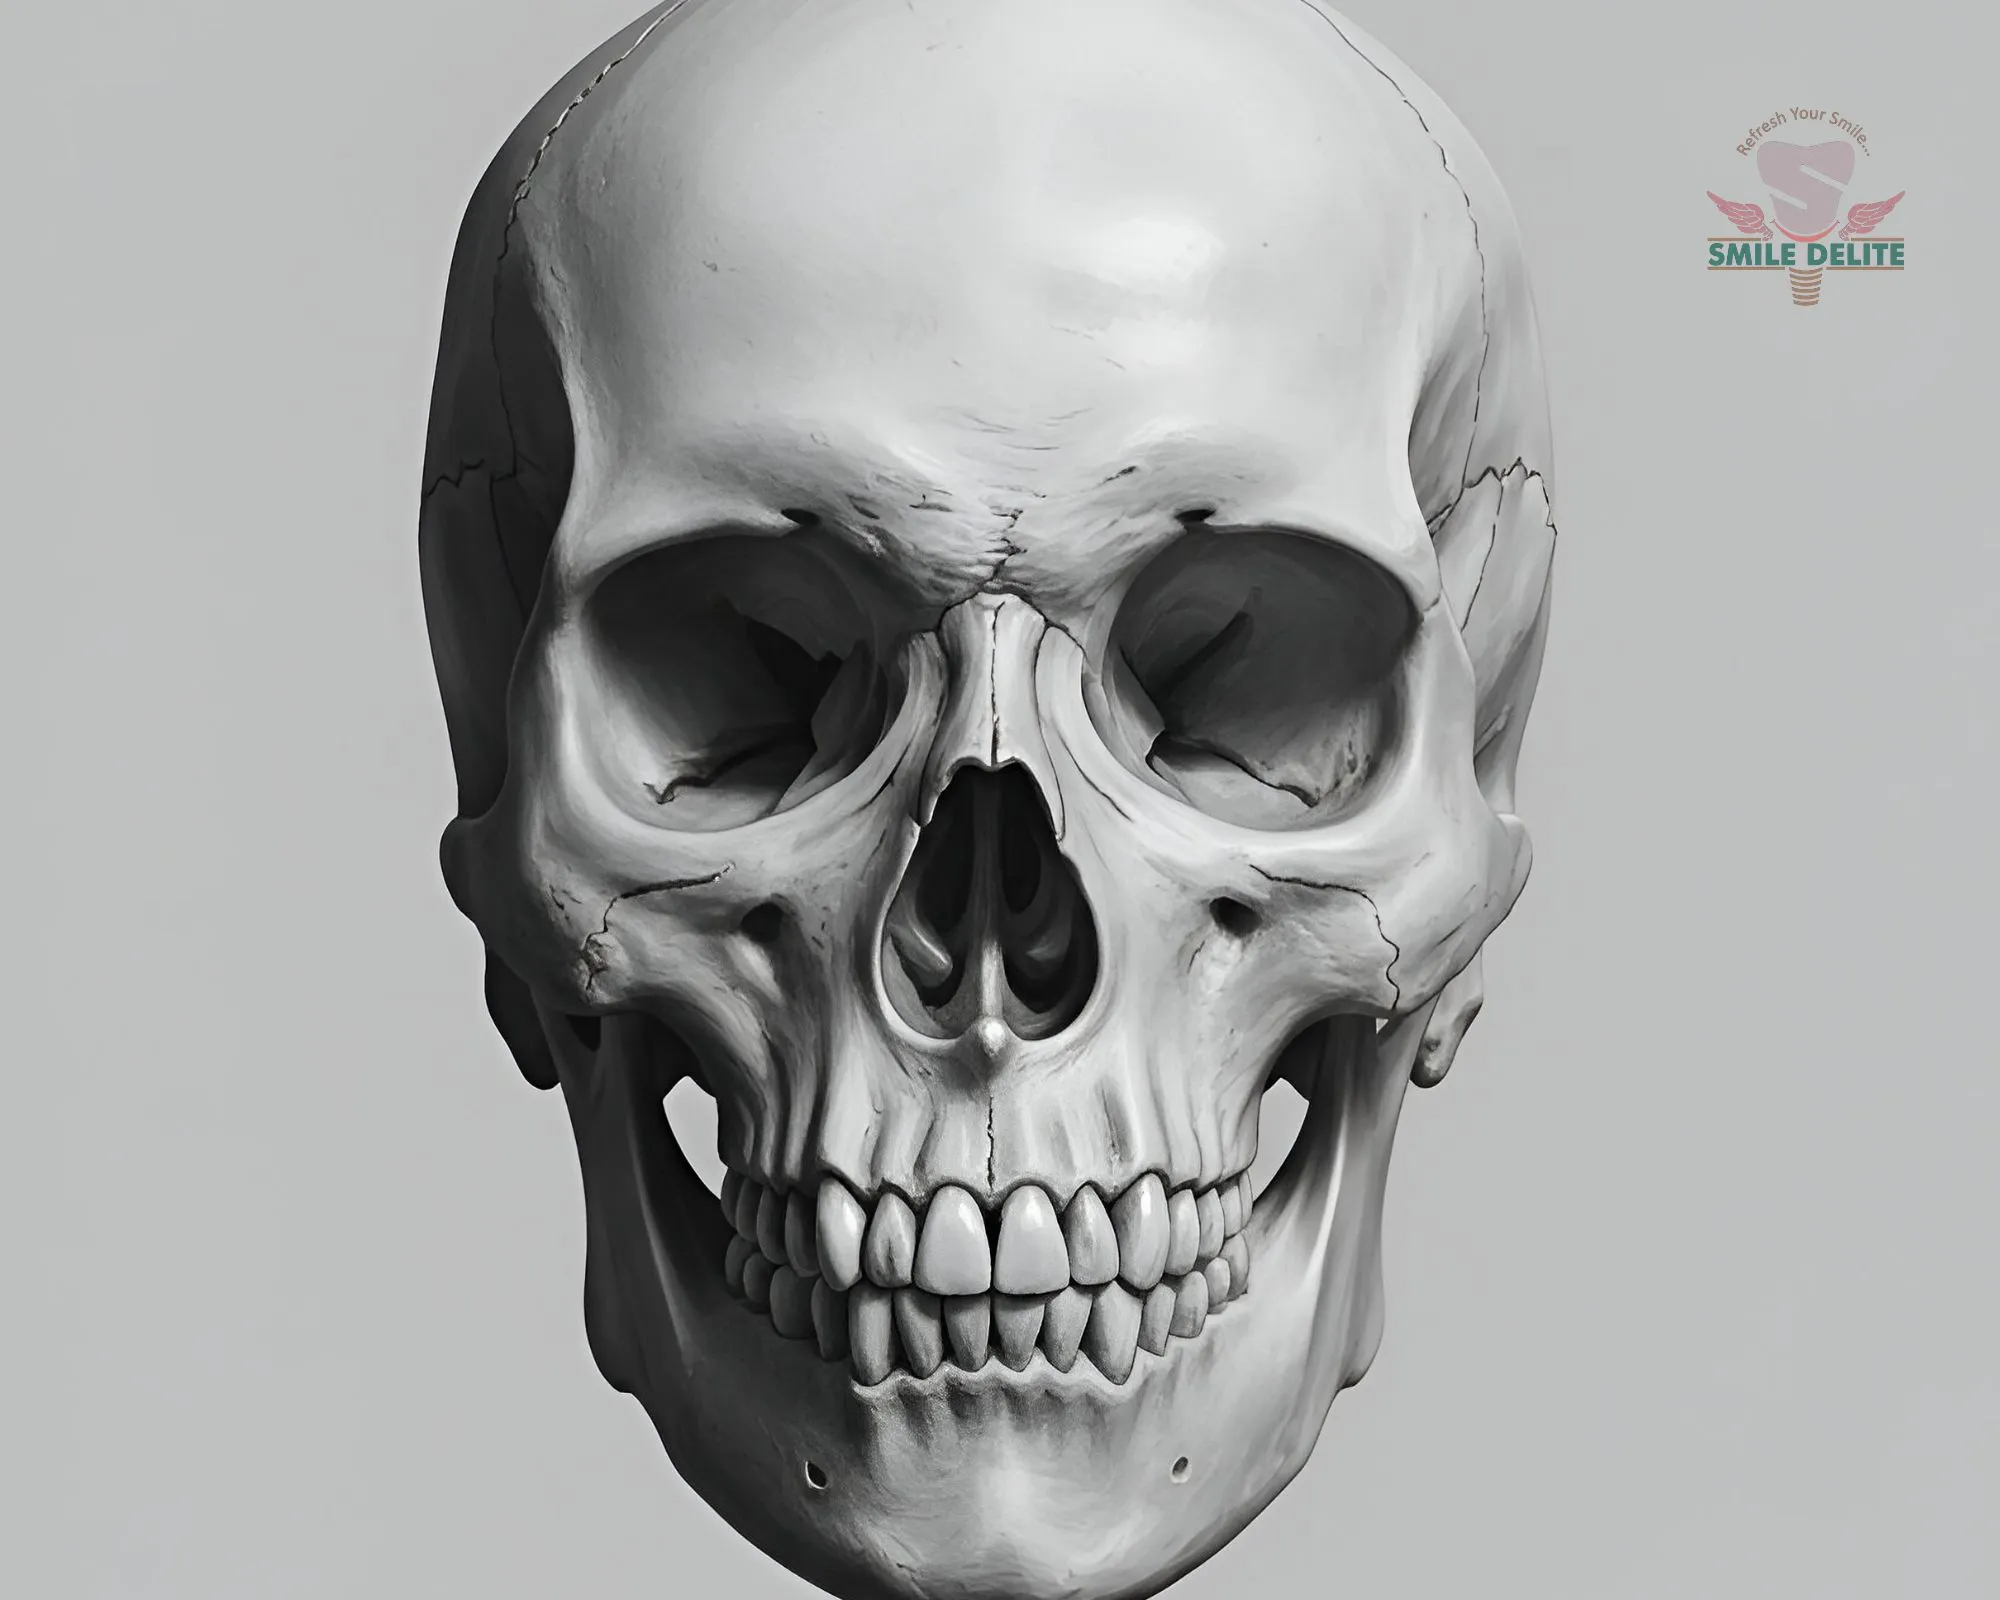

In-house digital imaging for accurate diagnosis and treatment planning.

Yes. SMILE D’ELITE has in-house OPG and CBCT imaging for accurate diagnosis and advanced treatment planning.